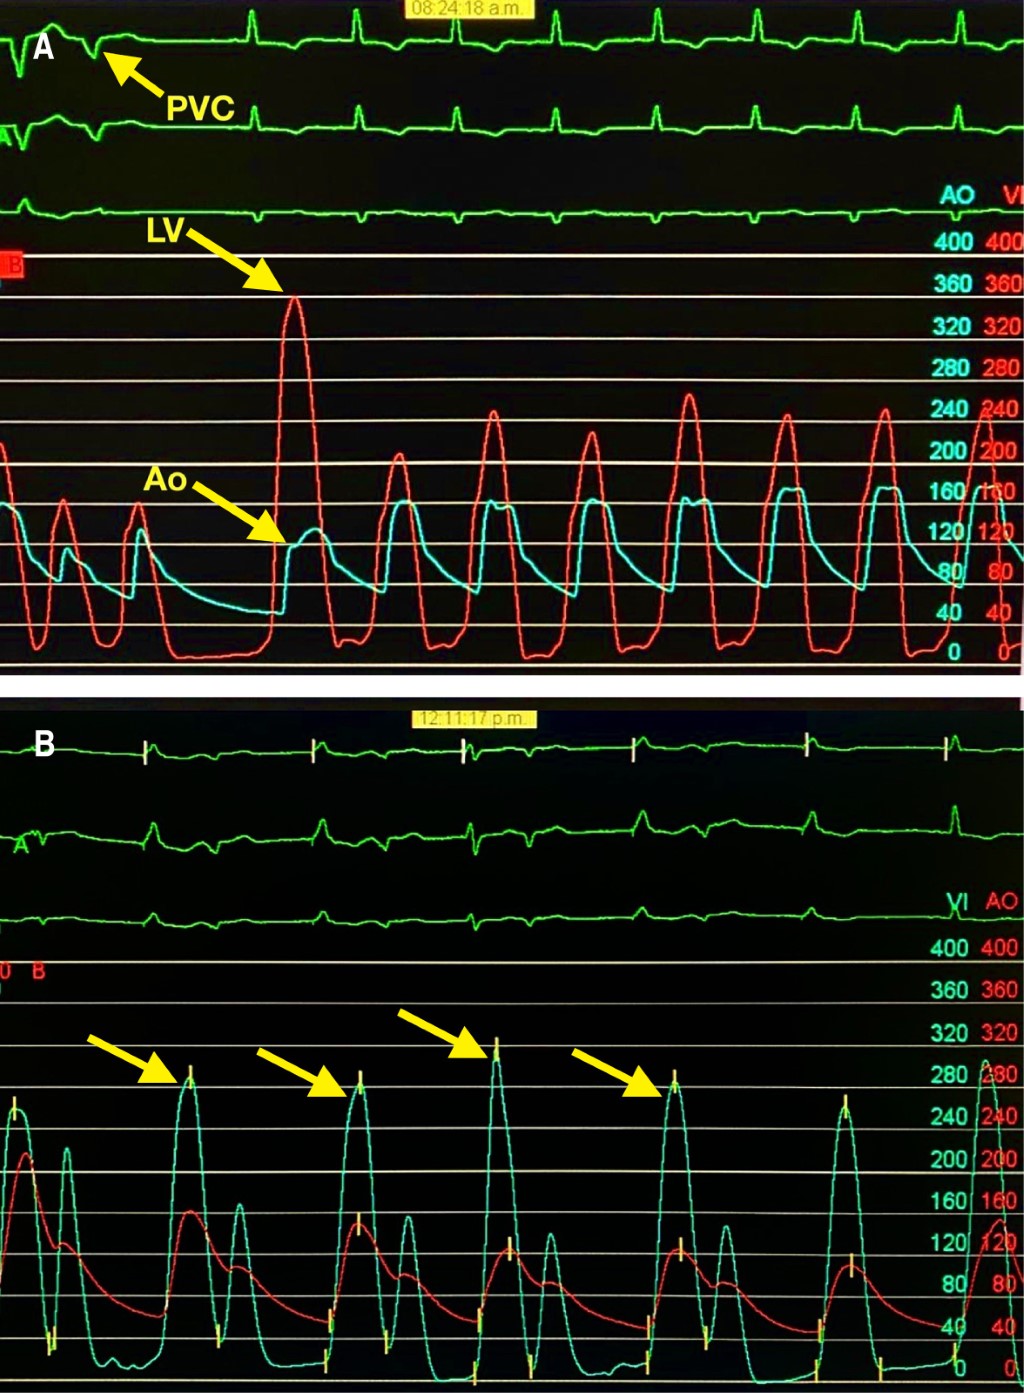

A new invasive coronary angiography showed epicardial arteries with no significant lesions (TIMI 3 flow grade). The left basal catheterization showed an aortic pressure of 160/65 mmHg, left ventricular pressure of 280/20 mmHg, and a resting gradient of 120 mmHg. A post-extrasystolic gradient of 240 mmHg was identified (Figures 1A and 1B), described as the Brockenbrough-Braunwald-Morrow sign, demonstrating the presence of left ventricular outflow tract (LVOT) obstruction.9

Due to the LVOT obstruction, the persistent symptoms, and the comorbidities previously mentioned, together, the hemodynamic, echocardiography, and cardiology teams decided to schedule the alcohol septal ablation. Through a trans-jugular approach, a temporary pacemaker was placed in the right ventricle. A guide was advanced through the left coronary artery to the first septal artery using a bilateral radial approach (Figure 3A), where an OTW balloon catheter was dilated (2.0 × 1.5 mm) until the complete occlusion was verified. With echocardiographic support, the right anatomical site was also confirmed. Initially, 7 ml of 70% ethanol was slowly injected, but only a partial occlusion was observed (Figure 3B); thus, an additional 3 mL injection was added, observing a complete embolization (Figure 3C). No complications in the anterior descending coronary artery or electrical abnormalities were detected, but it was decided to leave the pacemaker implanted on ventricular demand pacing. The post-extrasystolic intraventricular gradient was measured again, and a minimum residual gradient was recorded (aortic pressure of 160/55 mmHg, left ventricular pressure of 190/40 mmHg, and a peak gradient of 30 mmHg), while the resting gradient was absent (Figure 4). No periprocedural complications were presented.

Figure 1